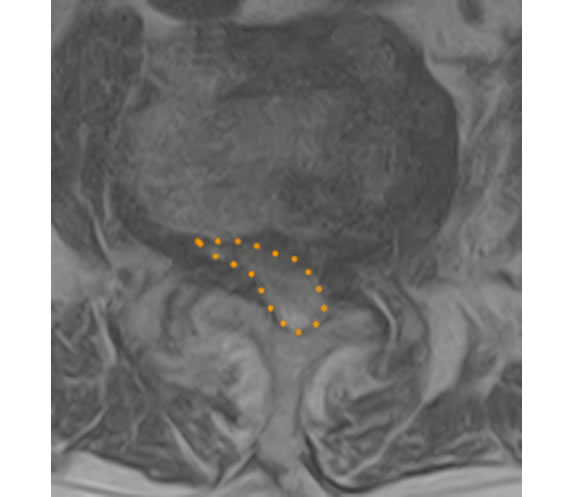

腰椎椎間板ヘルニア摘出前

摘出後